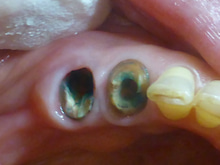

この薬は虫歯を染め出します。

そして 水で、洗い流します。

青く染まっている部分が虫歯です。

この部分を削り取ります。

何度か繰り返します。